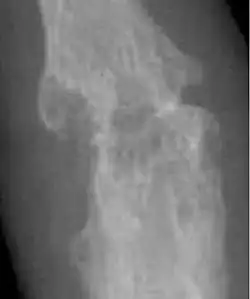

- Ankylosing spondylitis[18]

Arthritis types may also include ankylosing spondylitis, juvenile idiopathic arthritis, psoriatic arthritis, and reactive arthritis, among others.[2][6]

Osteoarthritis (OA) is the most common form of arthritis.[62] It affects humans and other animals, notably dogs, but also occurs in cats and horses. It can affect both the larger (i.e. knee, hip, shoulder, etc.) and the smaller joints (i.e. fingers, toes, foot, etc.) of the body. The disease is caused by daily wear and tear of the joint. This process can progress more rapidly as a result of injury to the joint. Osteoarthritis is caused by the break down of the smooth surface between two bones, known as cartilage, which can eventually lead to the two opposing bones coming in direct contact and eroding one another. OA symptoms typically begin with minor pain during physical activity, but can eventually progress to be present at rest. The pain can be debilitating and prevent one from doing activities that they would normally do as part of their daily routine. OA typically affects the weight-bearing joints, such as the back, knee and hip due to the mechanical nature of this disease process. Unlike rheumatoid arthritis, osteoarthritis is most commonly a disease of the elderly. The strongest predictor of osteoarthritis is increased age, likely due to the declining ability of chondrocytes to maintain the structural integrity of cartilage.[63] More than 30 percent of women have some degree of osteoarthritis by age 65. One of the primary tools for diagnosing OA are X-rays of the joint. Findings on X-ray that are consistent with OA include those with joint space narrowing (due to cartilage breakdown), bone spurs, sclerosis, and bone cysts.[64]